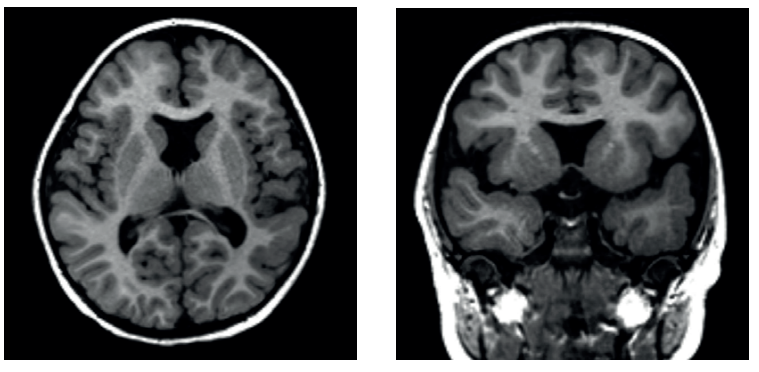

Heterotopias

Neurônios que interromperam a migração e ficaram “no meio do caminho”.

- Nodular Periventricular: Nódulos de substância cinzenta colados à parede dos ventrículos (é a forma mais comum).

- Em Banda (Córtex Duplo): Uma faixa de substância cinzenta no meio da substância branca, entre o ventrículo e o córtex.